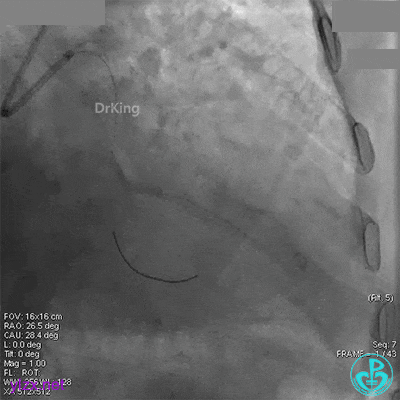

退出分支导丝后造影,血流不足3级。

术后心电图无明显改变。